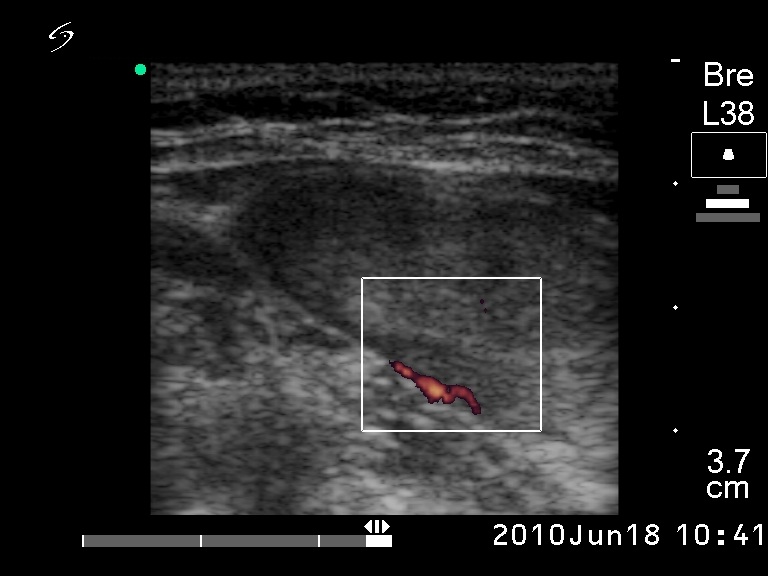

Ultrasonography: revealed a solitary hypoechogenic nodule with halo sign and perinodular blood flow.